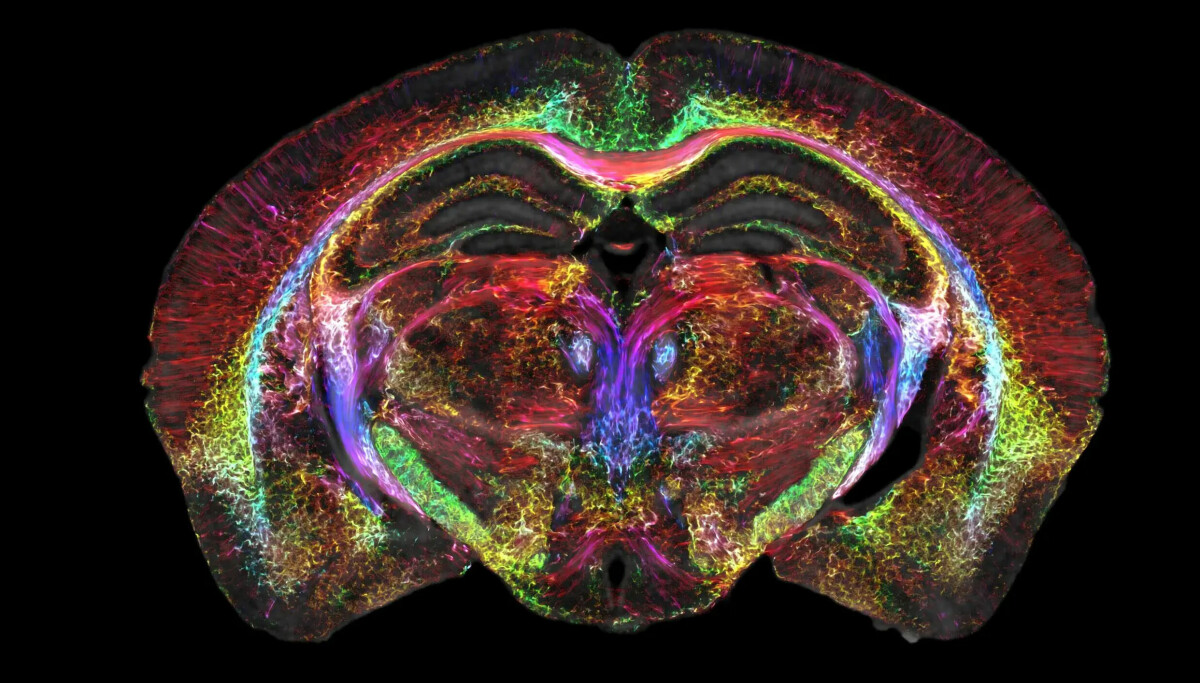

Cinquant'anni dopo la prima immagine scattata con la tecnologia MRI, i ricercatori della Duke University, in collaborazione con scienziati di diverse università, sono riusciti a creare un'immagine MRI che è 64 milioni di volte più chiara della tecnologia convenzionale.

La nuova tecnologia cattura i dati in tre dimensioni e crea i cosiddetti “voxel”, cioè pixel in tre dimensioni, dove la dimensione di ciascun elemento costitutivo dell'immagine è di soli 5 micron. Questo, tra l'altro, può aiutarci a capire cosa succede nel cervello affetto dalla malattia di Alzheimer.

Con l'aiuto di un magnete da 9,4 Tesla, fino a tre o quattro volte più potente dei magneti odierni, e la potenza di calcolo di un supercomputer più piccolo, i ricercatori sono stati in grado di catturare una sequenza di immagini di un intero cervello di topo, di cui vediamo una sezione Qui.